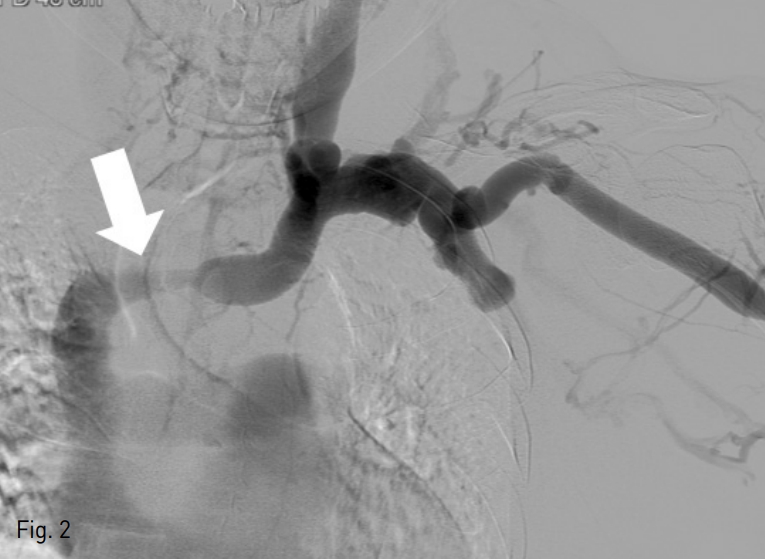

초음파 유도하에 좌측 상완부의 요측피정맥을 천자한 후 6 Fr sheath (Terumo, Tokyo, Japan)를 삽입함. 5 Fr KMP catheter (Cook, Bloomington, USA)를 좌측 무명정맥에 위치시킨 후 시행한 정맥조영술에서 무명정맥의 협착을 확인할 수 있음 (Fig. 2). 이에 12mm-4cm Mustang balloon catheter (Boston Scientific, Massachussets, USA)를 이용하여 무명정맥의 협착에 대해 풍선 확장술을 시행하였음. 그 후 14mm-3cm Niti-S vascular stent (TaeWoon medical, Gimpo, Korea)를 협착부위에 설치하였으나 스텐트가 상대정맥 (superior vena cava)으로 이동함 (Fig. 3).

Fig. 3

The stent migrated in to the superior vena cava because of insufficientstent fixation.